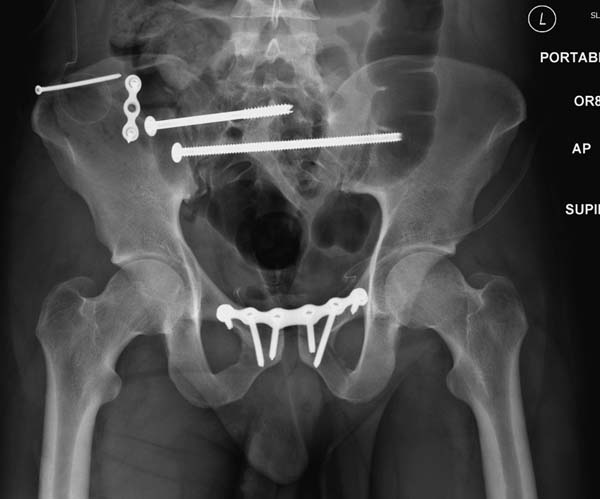

Большое спасибо всем Вам за помощь! Вчера прооперировали пациентку. Выполнили закрытую репозицию левой половины таза на тракционном столе под контролем ЭОП, закрытая фиксация левого КПС двумя каннулированными винтами. Учитывая удовлетворительное стояние отломков лонной и седалищной костей справа, а так же удовлетворительную ширину лона передние отделы стабилизировали системой ЦИТО

Послеоперационные КТ прилагаются

Винты введены в S1

Вроде бы все удалось. хорошо, что фрагмент (как выяснилось из КТ оказался небольшим), но для оценки лучше выкладывать рентген в стандартных проекциях